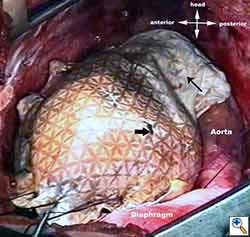

Medium and large-sized (Figures 1a, 1b) defects generally result after pneumonectomy for advanced central lung tumours which invade the pericardium (T3 invading pericardium), thus requiring reconstruction (Figure 1c). To achieve a curative resection, negative pericardial resection margins must be obtained and checked microscopically. More invasive tumours (T4 invading cardiac structures) require partial atrial resection and pericardiectomy associated with pneumonectomy.

| Figure 1c: Intraoperative aspect of pericardioplasty with Marlex mesh after right completion pneumonectomy with partial pericardiectomy. |

Video 1 depicts a pericardial reconstruction with Marlex after a right completion pneumonectomy with pericardiectomy for lung adenocarcinoma (see also Figure 1). The technique of pericardial reconstruction after the resection of invasive mediastinal tumours is illustrated in Figures 8a-c). Video 2 depicts a pericardial reconstruction with Mersilene mesh after the resection of a malignant thymoma invading the anterior pericardium (see also Figure 4b). The technique of right pericardial reconstruction after extrapleural pneumonectomy is illustrated in Figures 9a and 9b). Video 3 depicts a pericardial reconstruction using Gore-Tex Dual Mesh after a left extrapleural pneumonectomy (see also Figure 3). Care must be taken to prevent constriction (Figure 10).